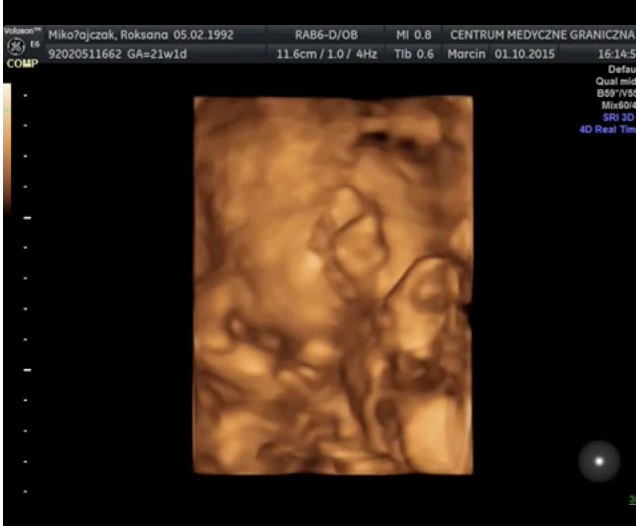

Wyniki badań prenatalnych są bardzo dobre. Obecnie trwa 23 tydzień ciąży, a mała waży 500 gram. Lekarz zalecił mi jednak kontrolę przepływu krwi, ponieważ obecne wyniki mieszczą się w górnej granicy normy 101cm/s. Wykonanie USG nie było wcale takie proste – maleńka Kasia jest bardzo ruchliwa i nie pozwalała się zmierzyć podczas badania. W czasie jego trwania udało się nagrać kilka krótkich filmów i zdjęć, możecie je zobaczyć poniżej. Kolejne badanie prenatalne odbędzie się 10-go grudnia. Termin porodu wyznaczono na 11 lutego i prawdopodobnie odbędzie się za pomocą cesarskiego cięcia.